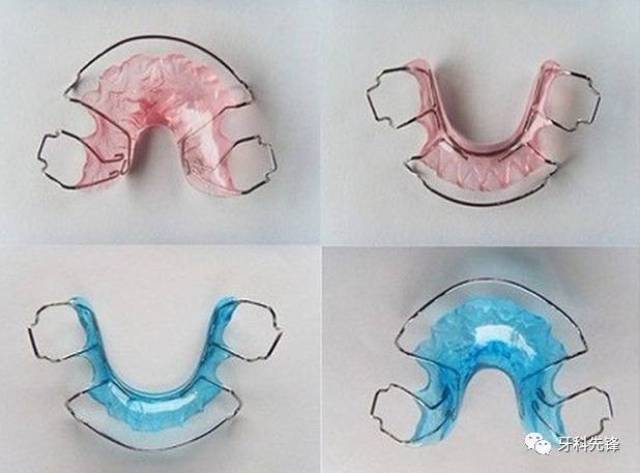

间隙保持器,

- 间隙保持器的应用

- 带环丝圈式间隙保持器临床应用

- 间隙固定式保持器2.jpg

- 6,牙早失时使用间隙保持器